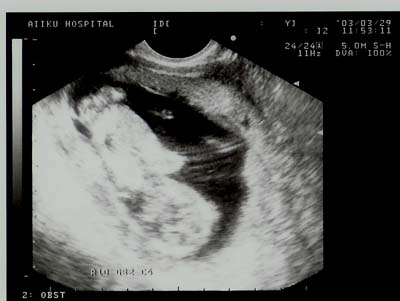

平成15年3月29日(土) 13週目

トモやはり寝ている。

産婦人科。

アタマが下です。

だいぶ大きくなりました。